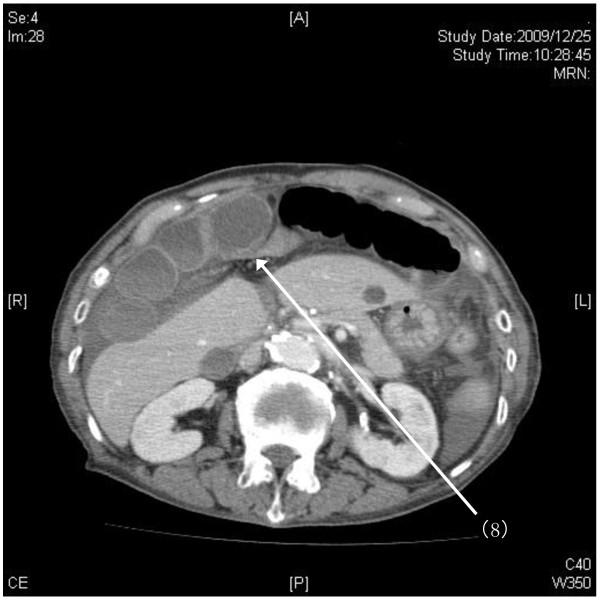

A 77-year-old Japanese woman presented to our emergency department with sudden hematemesis, occurring at least four to five times over a 12-hour period. No ulcer or gastrointestinal bleeding was detected on gastroendoscopy. A 40mm mass in the inferior lobe of the right lung was found on a chest X-ray, and our patient's symptoms were therefore initially ascribed to aspirated blood from lung tumor-associated hemoptysis. However, our patient continued to show signs of severe abdominal pain and decreased urine output despite aggressive hydration, leading her examining physicians to search for a possibly severe, occult abdominal pathology. On emergent computed tomography imaging, we found an acute strangulated internal hernia within the falciform ligament. Diagnosis was made by helical computed tomography, permitting rapid surgical intervention.

Our findings on computed tomography imaging assisted with the pre-operative diagnosis and enabled us to make a rapid surgical intervention. Early diagnosis may help preclude significant strangulation with unnecessary resection.